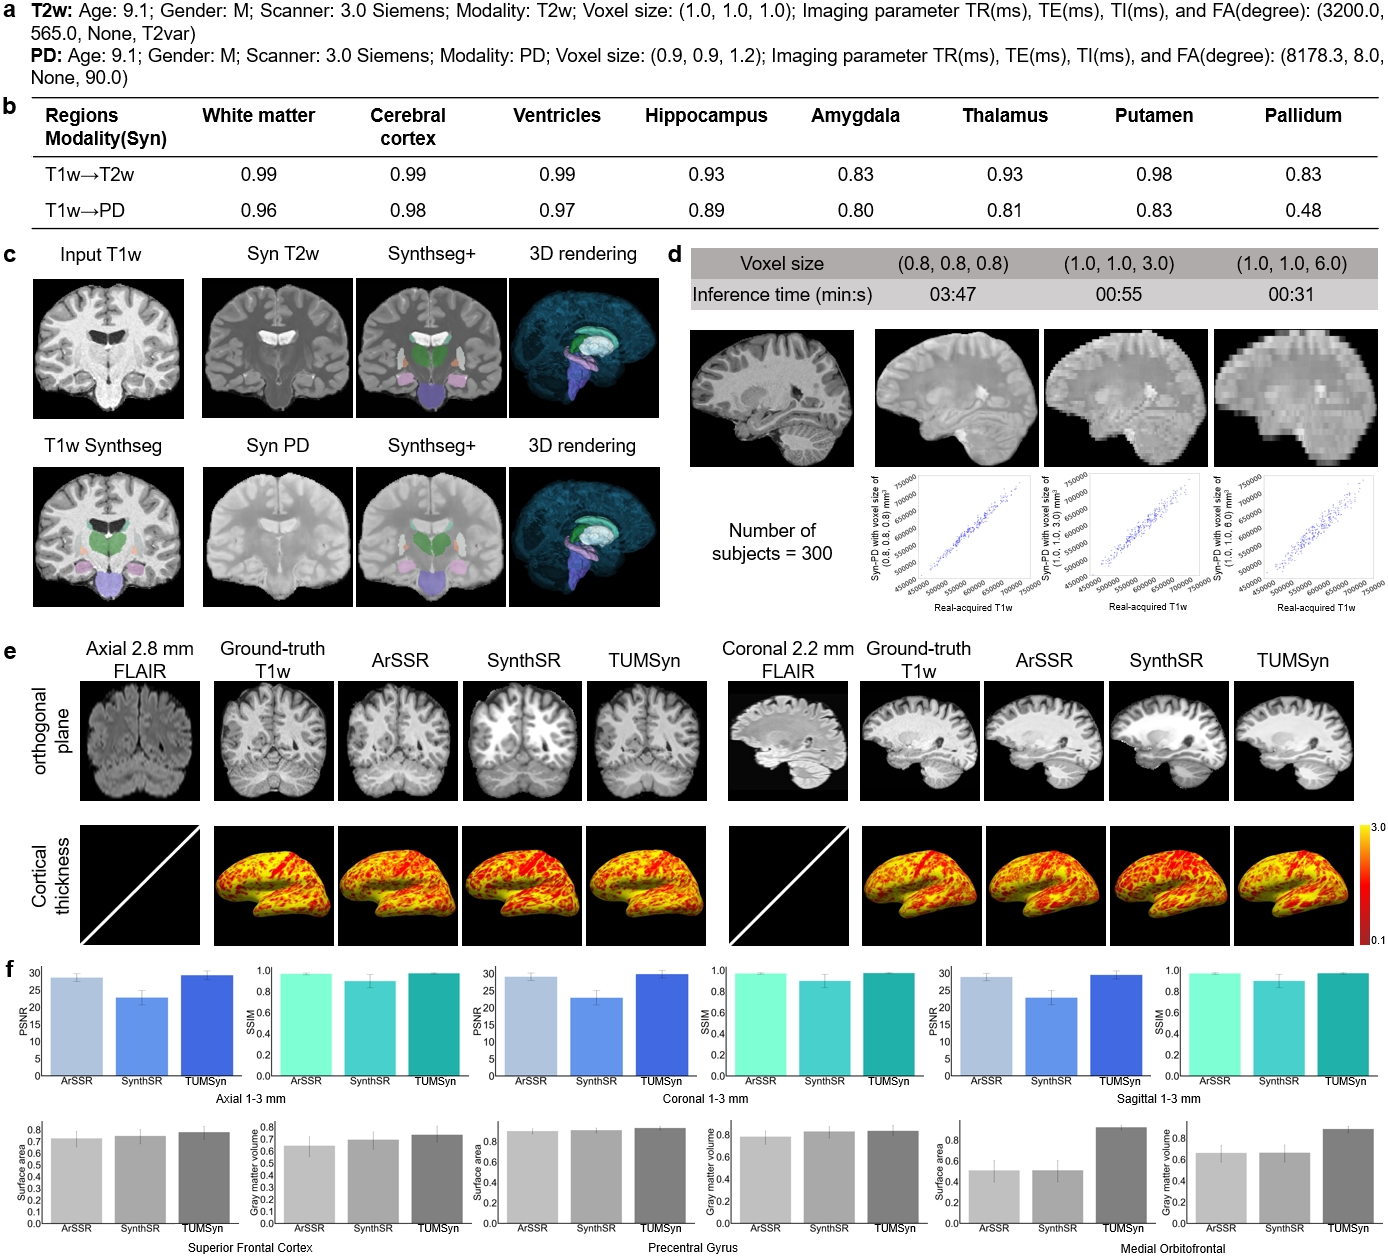

Visual evaluation is presented in Fig. 4. Besides the aforementioned comparison methods, a general method dedicated to synthesizing T1w images, SynthSR [28], is further enrolled into comparison. We observe that, since the PD images in the IXI dataset are acquired from two centers using different imaging protocols, the output images of TUMSyn are much more accurate in anatomical details especially compared to SC-GAN, One-hot model, and SynthSR (Fig. 4 a). These observations once again underscores the importance of utilizing imaging parameters and demographic information as textual prompts to guide accurate image synthesis.

Besides, we further perform whole-brain region parcellation on the HCP development (HCPD) dataset to assess the anatomical structure consistency between synthetic and real-acquired images (Fig. 4 b). Totally 30 brain regions are segmented using Synthseg+ [29]. We compare the parcellation results by our TUMSyn with those by other methods using visual inspection and Dice score. Both qualitative and quantitative evaluations reveal that the generated images by our TUMSyn enable the most precise parcellation.

Besides promising synthesis performance on MRI sequences that are acquired in practice, TUMSyn also exhibits its potential to supplement MRI sequences that are not acquired in real-world scenarios. We adopt 2,864 scans from the external ABCD dataset, which includes real T2w images while lacks proton density (PD) images. For PD image generation, we use the imaging parameters from the Guy’s center in the IXI dataset (Fig.5 a). Based on the provided text prompts, TUMSyn generates the T2w and PD images from the corresponding T1w scans. Since there is no ground-truth PD images in the ABCD dataset to directly verify the synthesis quality, we resort to segmentation consistency between the synthesized PD and the associated T1w image pair, measured by Pearson collection (Fig.5 b). We find that the segmented large regions, including white matter, cerebral cortex, and ventricles, are nearly identical to those obtained from real images. Other regions are also consistent with the real-acquired sequences. For instance, in real-acquired PD sequences, the putamen and pallidum show poor contrast with surrounding gray matter and more blurred boundaries compared to the T2w sequences, and we observe the same trend in our generated images, which is also proved by the decreased segmentation performance for these structures. Additionally, we visualize the synthesized PD images along with the corresponding segmentations (Fig.5 c), which show plausible structural and contrast characteristics as the PD sequences acquired in the IXI dataset. Moreover, in Fig.5 d, we can see that TUMSyn can generate PD sequences at varying voxel sizes with accurate anatomical structures in a much shorter time compared to real scanning.

Lastly, in addition to validating the cross-sequence generation and SR performance of TUMSyn on real input data, we also simulate more diverse input data with various spatial resolutions and scanning orientations, to further demonstrate the model’s ability in handling heterogeneous data. We adopt 300 paired T1w and FLAIR images from the external UK Biobank dataset, and then simulate FLAIR images under various text prompts. Details of the simulation process are available in the Methods section. Besides SynthSR, TUMSyn is also compared with ArSSR [30], which is an SR model that can support arbitrary-scale upsampling and particularly trained on this dataset. Notably, across all the three simulated FLAIR images, TUMSyn achieves the best performance in terms of PSNR and SSIM. For example, compared to ArSSR, TUMSyn improves PSNR of images scanned in the coronal direction from 29.08 dB to 29.81 dB. Our method outperforms SynthSR by up to 23.2% (from 22.91 dB to 29.82 dB) in PSNR (Fig.5 f). Further analysis on cerebral cortex synthesis, including superior frontal cortex, precentral gyrus, and medial orbitofrontal regions, focusing on cortical surface area (SA) and gray matter volume (GV), exhibit the same trend. The interclass correlation coefficient (ICC) with the 95% confidence interval (CI) is calculated between the synthesized T1w images and the real-acquired T1w images in these three cortical regions. Morphological analysis shows close matching between TUMSyn-synthesized images and real images with the minimal ICC value of 0.736 (95% CI 0.666-0.794) and the maximal ICC value of 0.932 (95% CI 0.911-0.948), demonstrating the ability of TUMSyn in providing superior anatomical structures even in zero-shot inference (Fig.5 f).